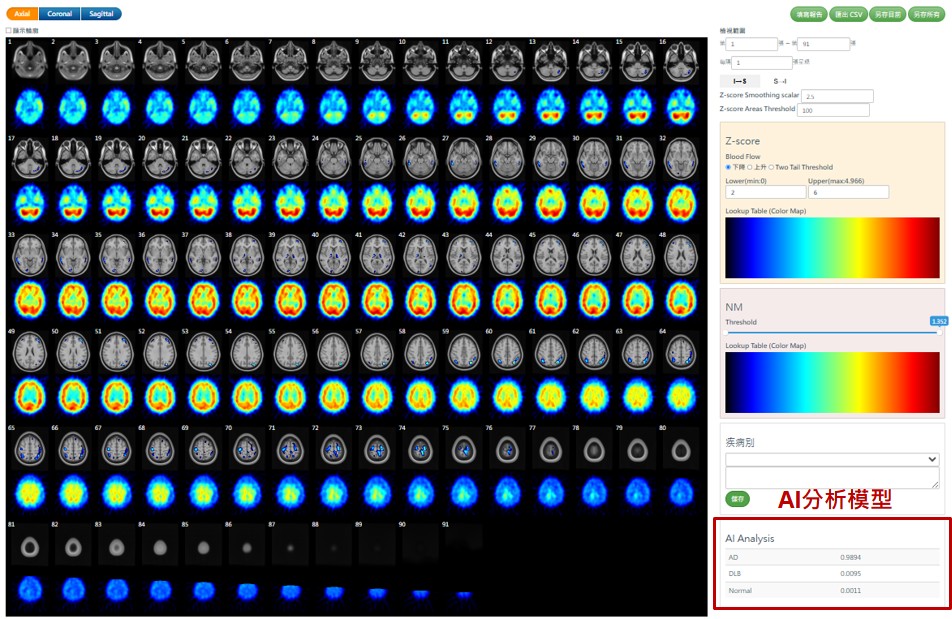

國原院近年投入智慧醫療研發,開發出腦血流影像異常分析軟體「ECDaim」,可自動判讀核醫影像、標示細微異常區域,顯著提升臨床效率與準確度。研究團隊更利用專利技術與機器學習演算法,建立可依年齡調整的常模模板,解決不同儀器間的影像差異問題。

系統可依個案年齡自動比對相對應的正常人腦功能影像資料庫,提升分析的準確性與臨床判讀效率(圖/亞東醫院提供)

亞東醫院核子醫學科主任醫師汪姍瑩指出,核醫分子影像能反映失智症早期的腦部血流變化,AI輔助系統導入後,可自動生成半定量Z-score分析報告與三維定位圖,讓醫師更快、更精準辨識異常區域。臨床驗證顯示,AI判讀與專家一致性高達九成以上,顯示人工智慧已能穩定融入診斷流程。

阿茲海默症患者腦部八向表面投影影像,藉由多角度分析可突顯異常血流分布區域,輔助醫師精準判讀。(圖/亞東醫院提供)